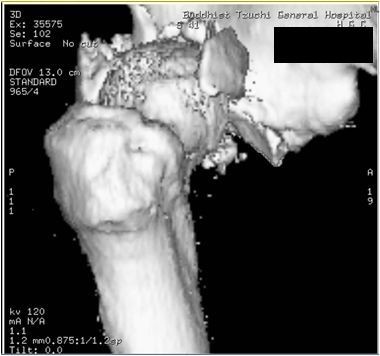

圖:鄺世通醫師分享當時洪國程先生右腳多處粉碎性骨折。

而當時的主治醫師就是個性直率低調,被同事與後進同仁暱稱為鄺爺的骨科鄺世通醫師,這個在鄺醫師口中的小骨折,其實是包含髖關節、大腿股骨、膝蓋髕骨、與小腿脛骨等多處粉碎性骨折的複雜個案,不論是X光檢查,還是電腦斷層檢查,都能看見因為強力撞擊穿出髖關節的股骨,還有粉碎的髕骨,歷經數個小時的開刀,才救回洪國程先生的性命與右腿。